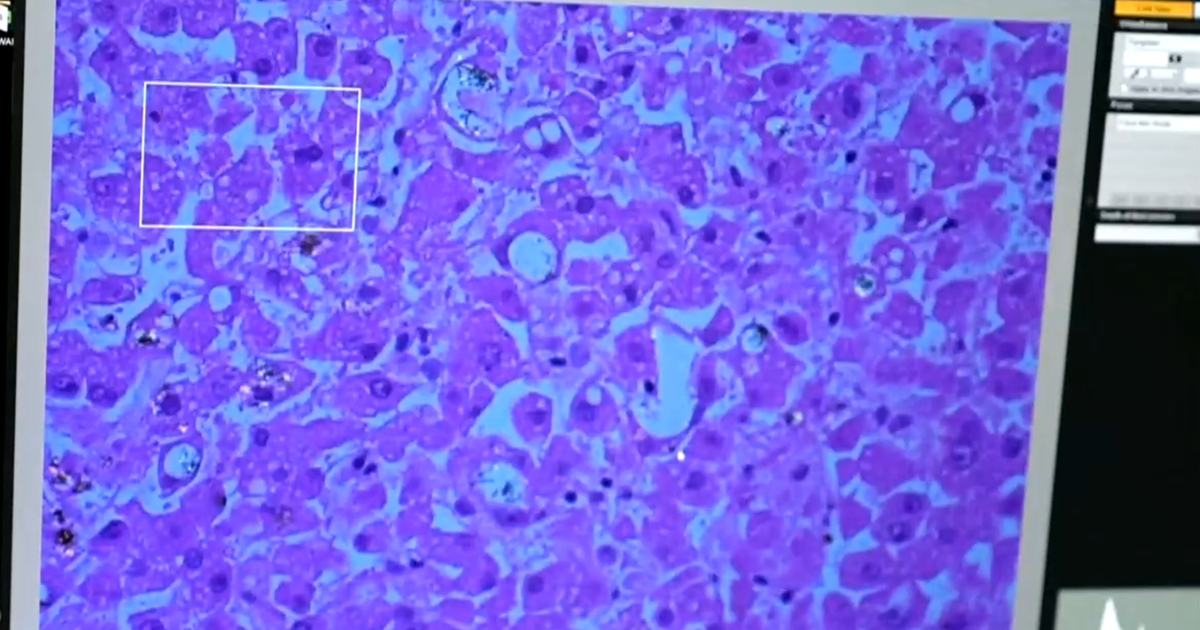

Albuquerque, New Mexico — Dr. Matt Campen studies the health effects of environmental pollutants. His lab at the University of New Mexico has, for the first time, found plastics in human brain tissue.He says his research estimates that the amount of plastic in the brain could be roughly equal to the size of a plastic spoon. “That is a lot,” Campen explains to CBS News. “…The fact that it’s getting worse over time is really the issue.” Scientists believe these microscopic particles, called nanoplastics, come from all the plastic people use and throw away. When plastic breaks down over time, it winds up in the food supply, the water we drink, and even the air we breathe.A study last month in the Journal of the American Heart Association finds that people living near nanoplastic-polluted oceans are more likely to suffer from type 2 diabetes, heart disease, and stroke compared to those that lived near waters that have low levels of nanoplastics.

Campen’s lab has found more plastic in the brains of people with dementia than those without dementia.Now, research on these nanoplastics is moving out of the lab and into long-term clinical studies. “We have more evidence now for the effects of plastic on children’s chronic disease then we do on food dyes,” said Dr. Leonardo Trasande, a professor of pediatrics at New York University’s Grossman School of Medicine. “And if we use the same evidence standard, we should be acting as fiercely on plastics in the food supply as we are on food dyes.” Trasande is tracking plastics’ impact on over 64,000 children, from pregnancy to adolescence, including on 8-year-old Jack Glaser.”The amount of information that they’re collecting is remarkable,” Glaser’s mother, Tammy Fried-Glaser, said. “They did cognitive studies on Jack, you know, height and weight and sonograms, and beyond.”So far, Trasande’s research has linked plastics to health problems like hormonal issues with fertility, premature birth, cognitive abnormalities and cardiovascular disease.

“Literally the particle is a problem — because it’s a foreign body in a tissue,” Trasande said. “It might thrash the lining of the coronary artery, contributing to clogging…These are toxic drug delivery systems.” While the details are still emerging, experts agree that less plastic is the way forward.